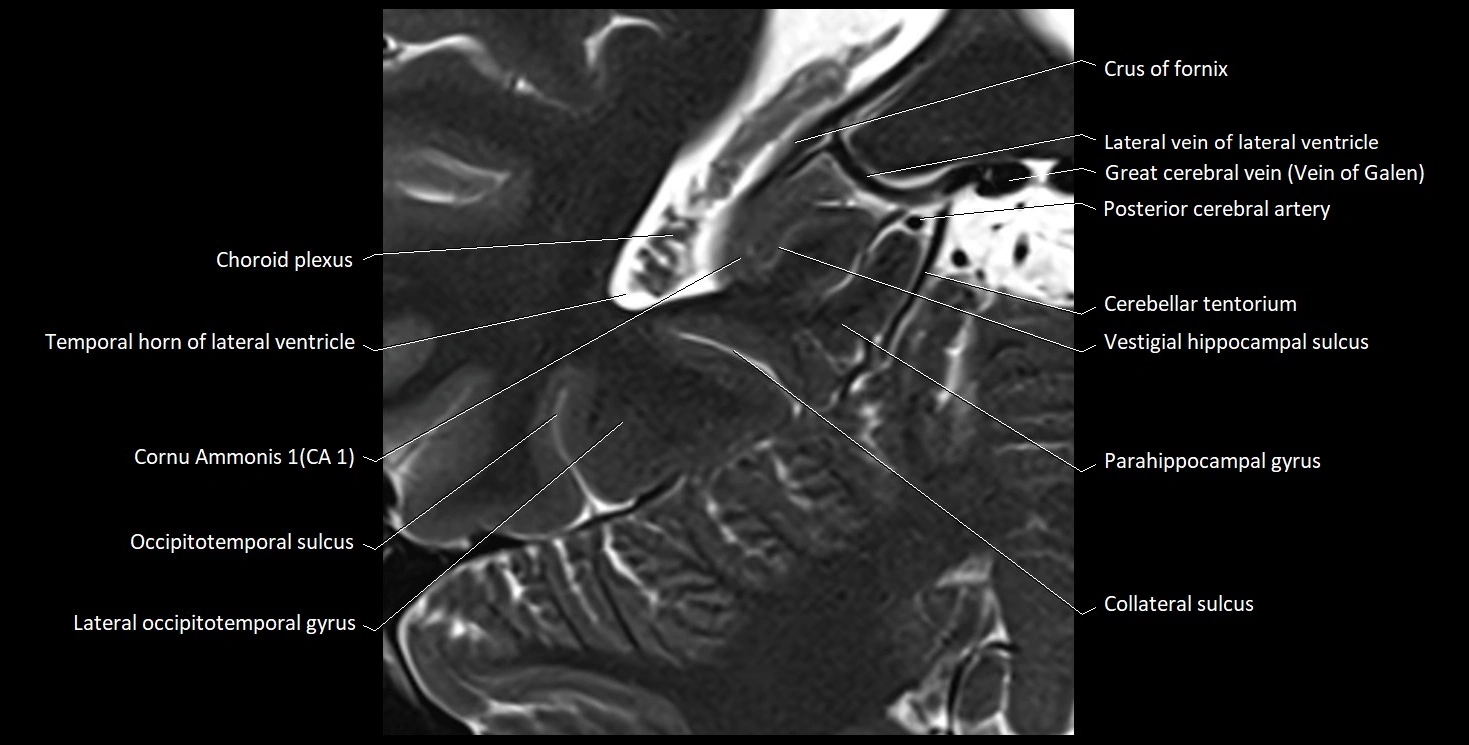

MRI images

image